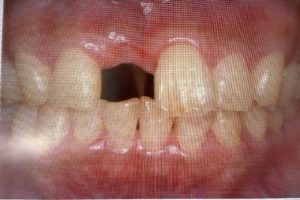

ITインプラントが得意とするのは骨が薄い症例です。特に普通のメーカーでは難しい症例に対して、直径2.2ミリや直径2.8ミリの細いインプラントが使えることです。他のメーカーでは直径3.0ミリが最少となります。

後は歯茎からの貫通部が細いためにインプラント周囲炎になりにくく、歯茎も下がりにくいという特徴があります。